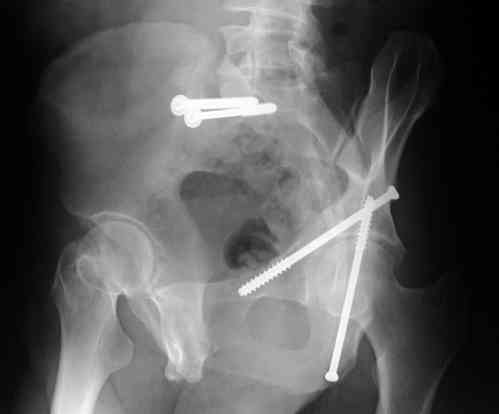

For Alex... here are some cannulated and 7mm screws for you... notice the fracture malreduction as indicated by the head subluxation on both views...this was a percutaneous technique without open reduction... I don¹t like it but there it is... the fixation technique is not at fault, because there was no open reduction of the fracture... but let¹s not get in to all that.